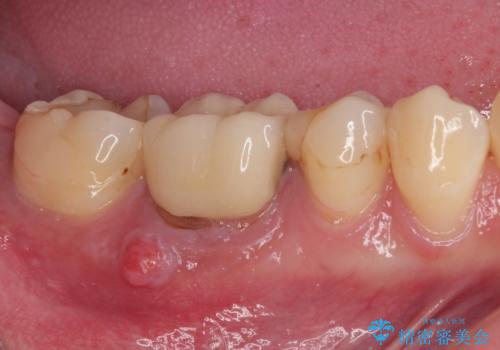

- 前歯のデコボコと変色した前歯を気にして来院された患者様です。

舌の突出癖により治療期間中に開咬となり、治療が長引きましたが、口元も治療前よりも引っ込めることができ、すっきりとした仕上がりとなりました。